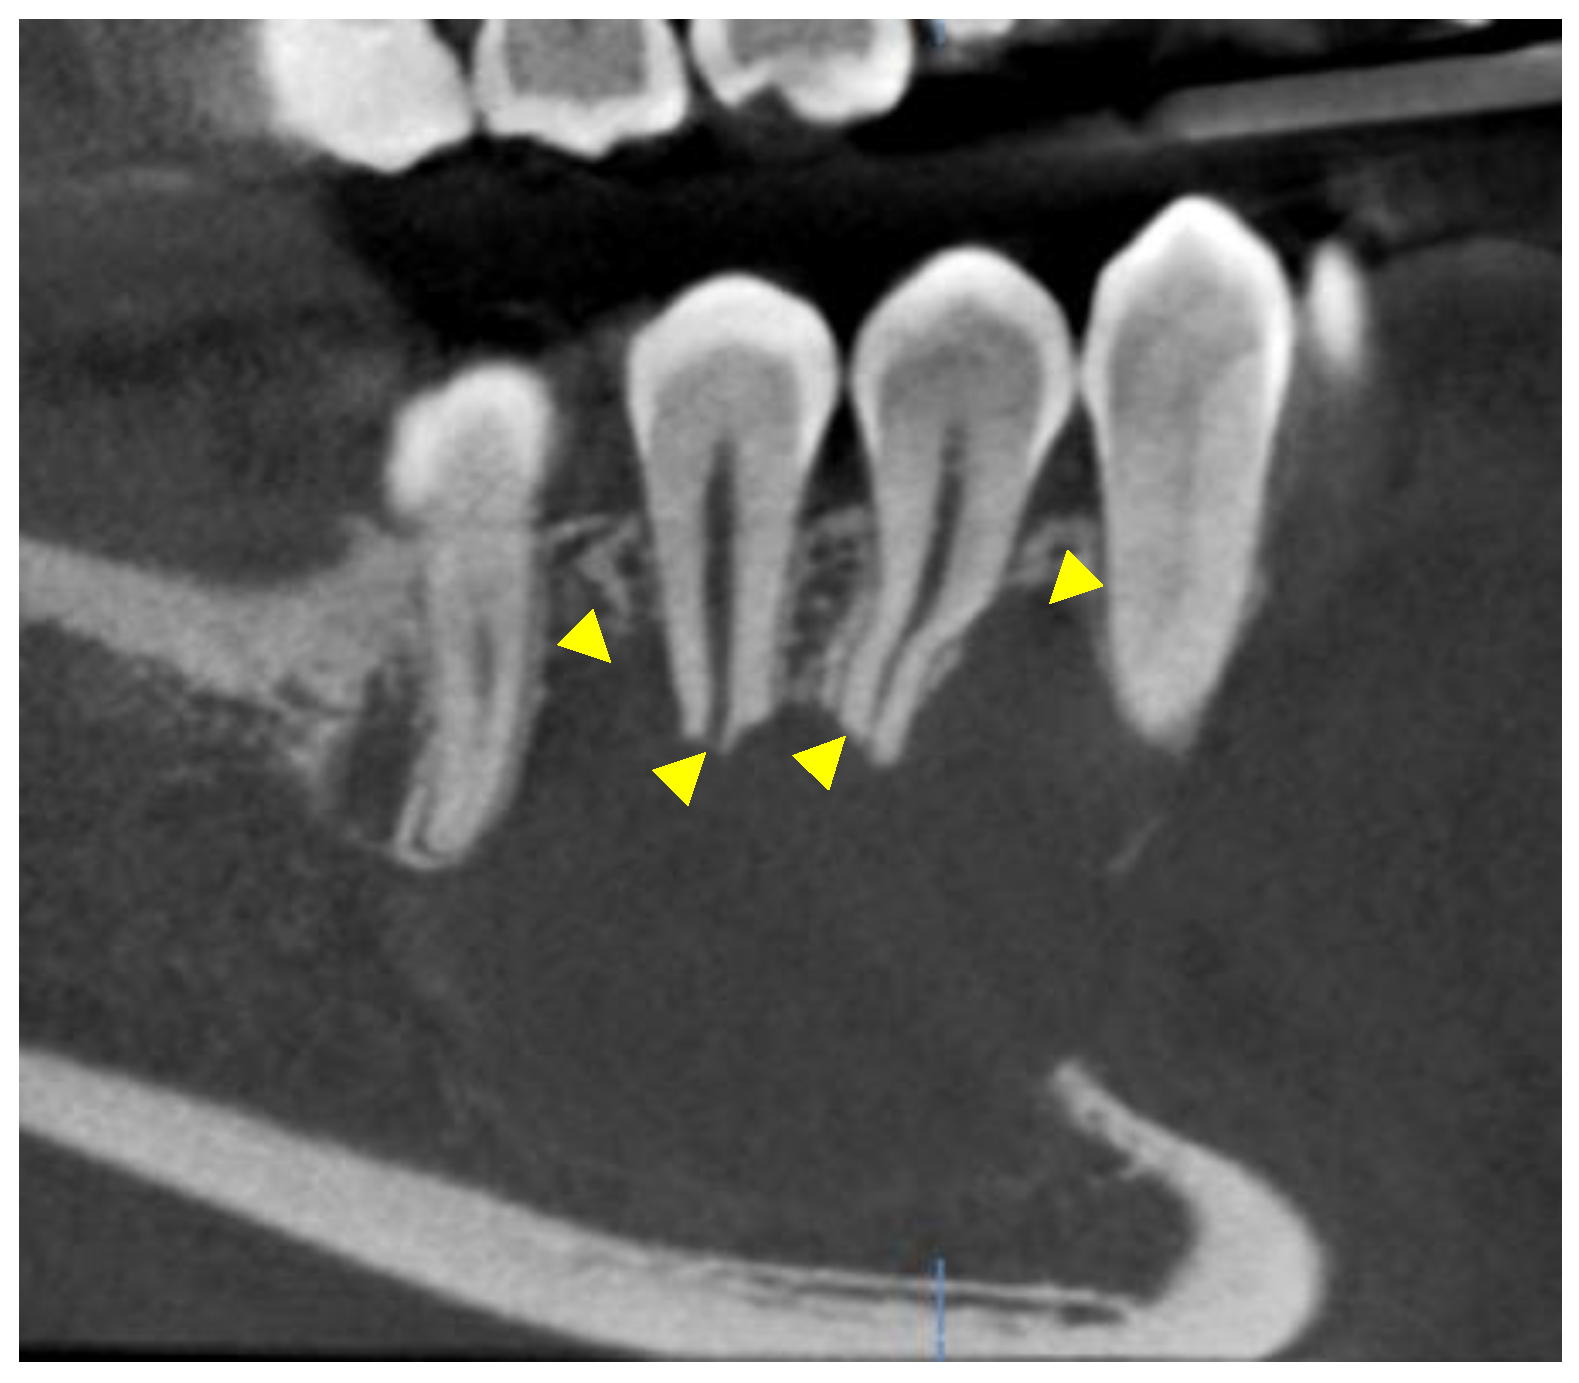

A young male presented in the Urgent Care Clinic at Boston University Henry M. Goldman School of Dental Medicine with a panoramic radiograph, seeking dental care due to numbness in the lower right region of his mandible. His dentist had referred him for a root canal treatment (Figure 1).

Figure 1. The yellow arrowhead shows a unilocular lesion detected in the area of #27–30.